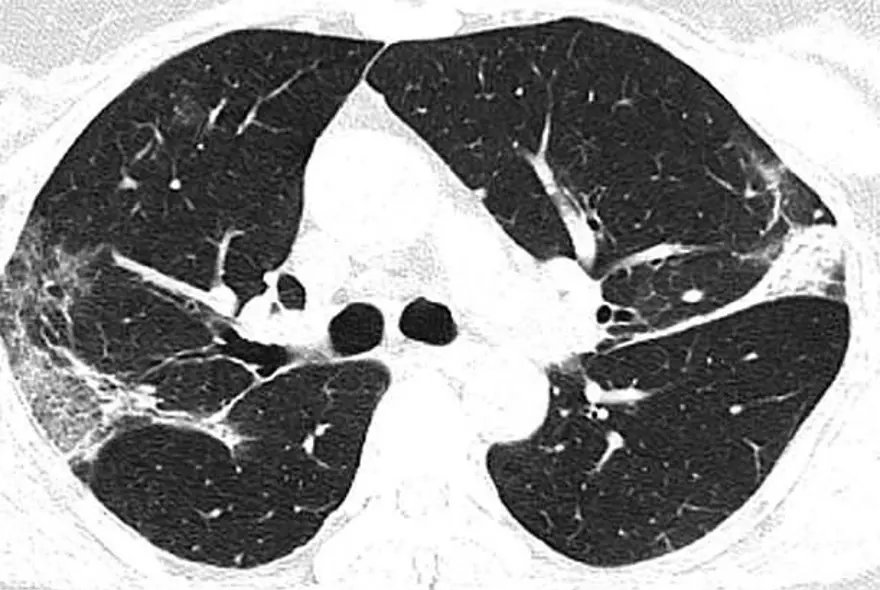

Wuhan'a seyahat ettikten sonra corona virüse yakalanan 54 yaşında bir kadının bilgisayarlı tomografi taramaları da akciğerlerinde hava boşluklarının kısmen dolduğunu gösteriyor.